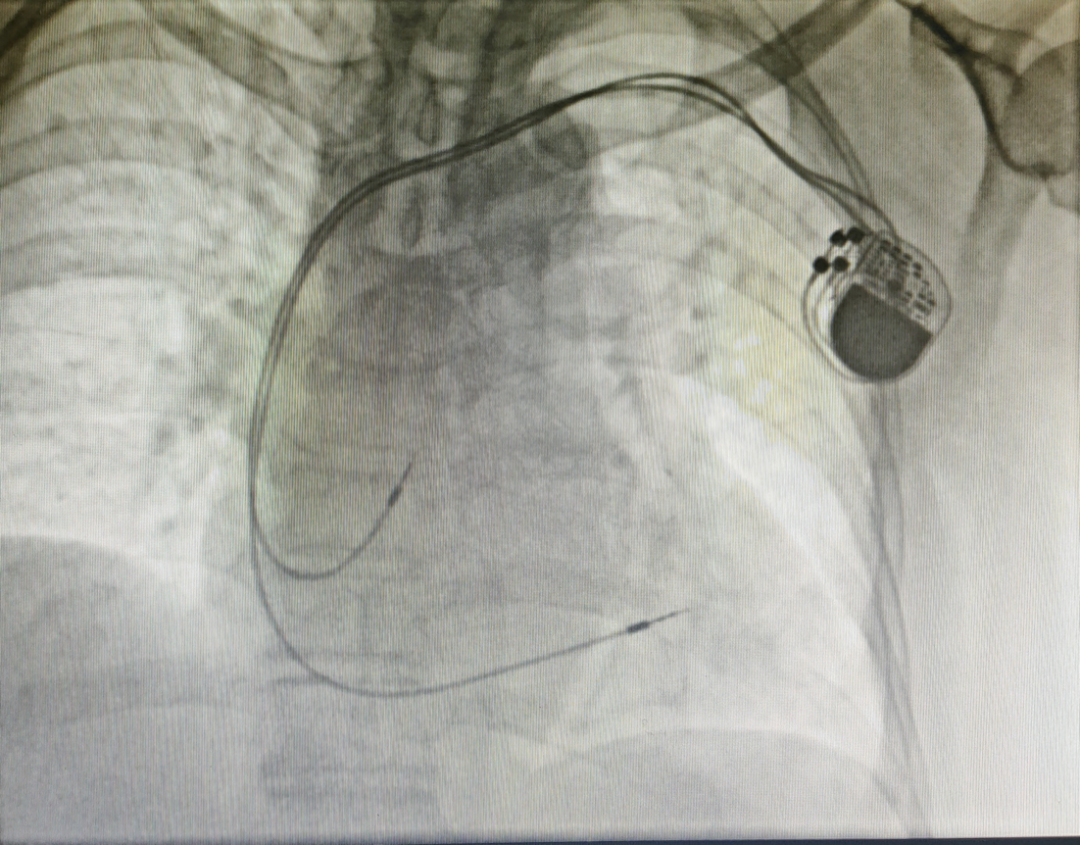

贺业健教授为患者植入首款国产磁共振兼容起搏器

植入后的图像